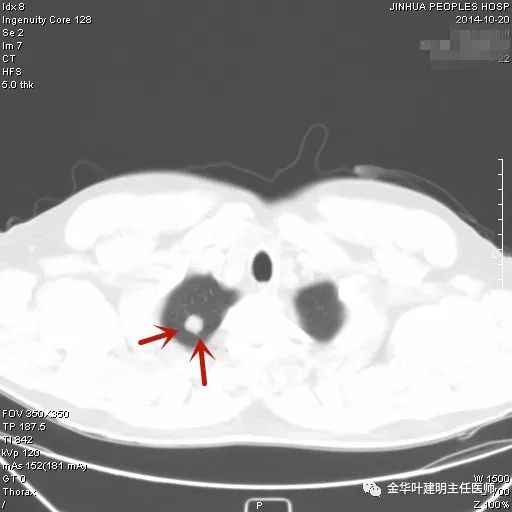

上图示典型的肺内淋巴结影像。靠近胸膜,高密度,三角形工多边形,相对比较孤立,周围没有炎性渗出或卫星灶,邻近胸膜(包括叶间胸膜)但无胸膜牵拉凹陷。